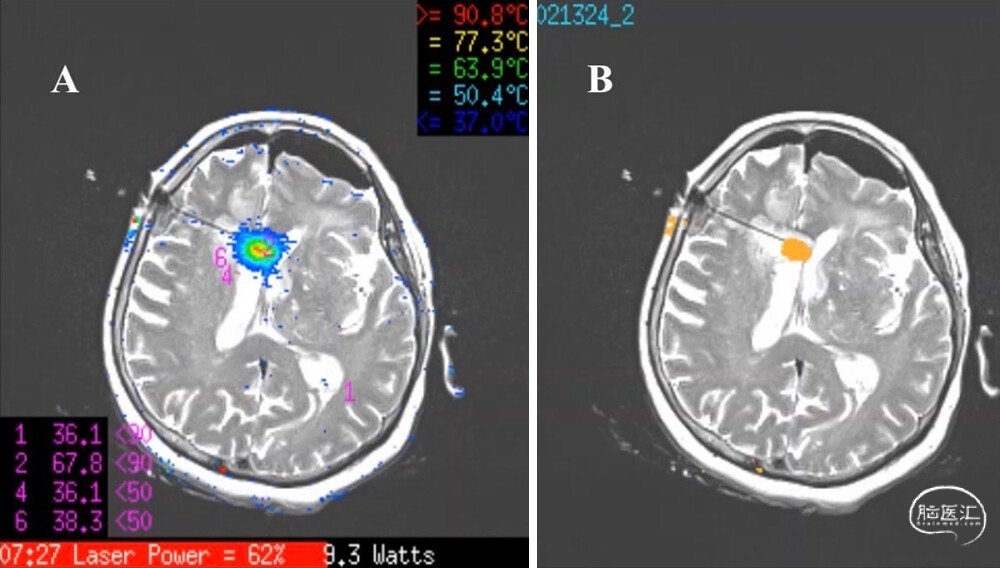

1.同期开颅切除+LITT:患者接受全身麻醉,在神经导航系统(StealthStation S8, Medtronic)引导下,采用荧光素钠辅助开颅切除左侧额叶病灶,冰冻切片病理结果符合GBM。随后通过Autoguide机器人平台(Medtronic),沿术前规划路径将Visualase激光导管置入右侧脑室旁病灶。手术同期,患者直接由手术室转入MRI检查室。将Visualase软件与MRI系统对接,激光导管及冷却系统连接至Visualase控制台,针对病灶设定专属温度限值与邻近功能区热安全阈值后,以低功率启动消融以评估热场分布,随后提高功率并持续进行导管冷却灌注,通过两次回撤操作完成消融,全程约3分钟,平均功率9.5瓦,以实现最大安全消融范围(图3)。

2.辅助治疗:术后MRI显示额叶病灶全切,脑室旁病灶达到近完全消融,消融范围(EOA)为93%(图4)。最终病理证实为IDH野生型GBM。患者术后第2天出院,未出现新发神经功能缺损。术后2周按照Stupp方案启动辅助放化疗,对两个治疗区域同步实施替莫唑胺化疗(每日75 mg/m²)联合分割放疗(60 Gy/30次)。

图4:MRI实时测温引导下LITT。A:T2加权像叠加热分布图,显示术中温度分布,红色区域为最大热损伤区,激光导管尖端峰值温度达90.8℃。B:消融完成后的最终热凝固区域。